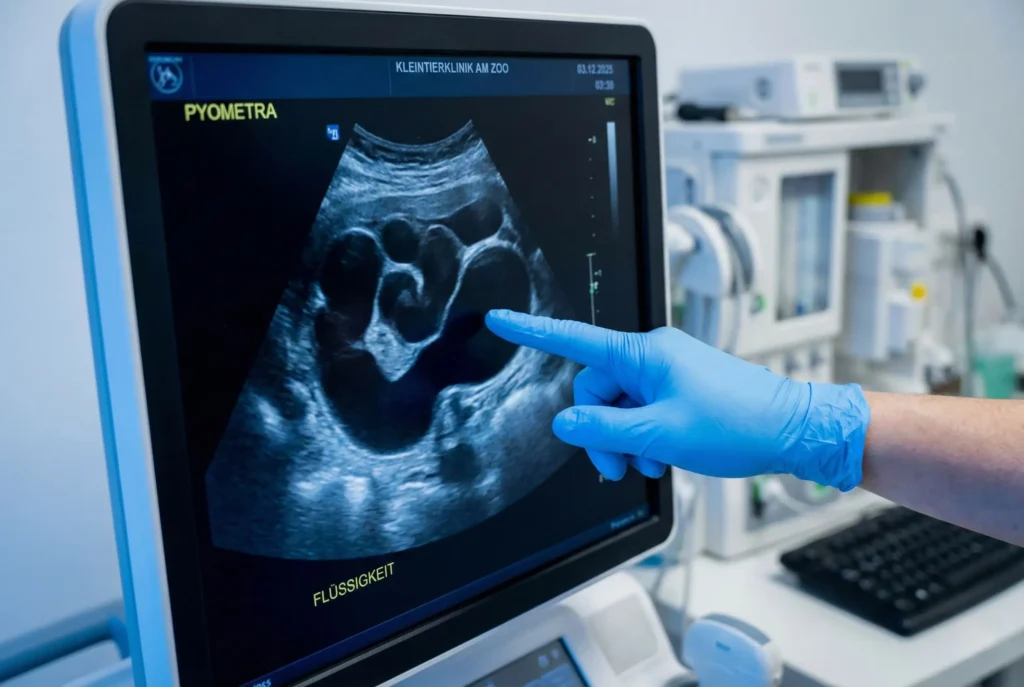

- Formen: „Offen“ (Eiter fließt ab) vs. „Geschlossen“ (Eiter sammelt sich im Bauch -> Platzgefahr).

Der Muttermund ist fest verschlossen. Der Eiter sammelt sich in der Gebärmutter, die sich wie ein Ballon füllt. Bakteriengifte gelangen ins Blut (Endotoxämie).

Gefahr: Sie sehen KEINEN Ausfluss. Die Hündin wirkt „nur“ krank. Wenn die Gebärmutterwand dem Druck nachgibt und reißt (Ruptur), ergießt sich der Eiter in den Bauchraum. Das ist meist das Todesurteil.